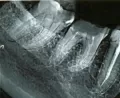

Я пошла в другую частную стоматологию, где мне сделали рентген и сказали, что зуб перфорирован и лечению не подлежит, необходимо его удалять. Изначально 5 зуб был совершенно здоров. Стоматолог своей вины не признает и уверяет, что зуб можно спасти.

По снимку видна или трещина или перфорация корня. Корневой канал не пройден, не расширен, не обработан и не запломбирован, поэтому есть риск в будущем возникновения воспаления за верхушкой корня зуба. Лучше не рисковать, а удалить зуб. Но если доктор даёт гарантии на своё эндодонтическое лечение и после гарантию на 1 - 3 года на функциональное и качественное протезирование, то можно попытаться сохранить зуб